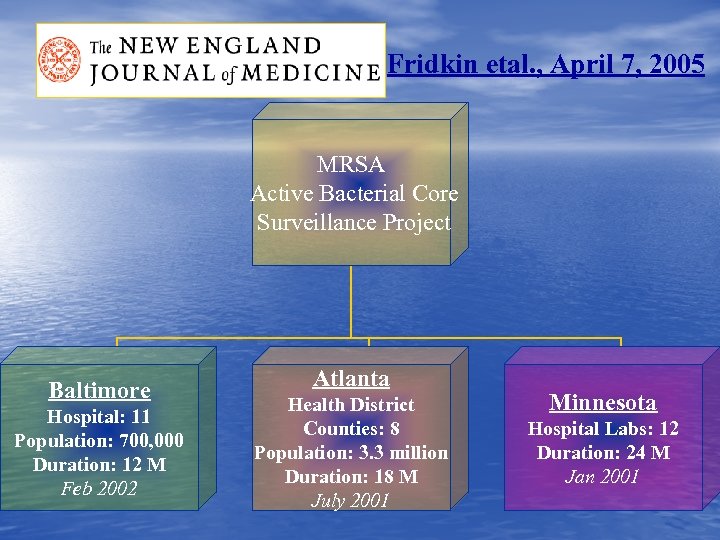

Fridkin etal. , April 7, 2005 MRSA Active Bacterial Core Surveillance Project Baltimore Hospital: 11 Population: 700, 000 Duration: 12 M Feb 2002 Atlanta Health District Counties: 8 Population: 3. 3 million Duration: 18 M July 2001 Minnesota Hospital Labs: 12 Duration: 24 M Jan 2001

Fridkin etal. , April 7, 2005 MRSA Active Bacterial Core Surveillance Project Baltimore Hospital: 11 Population: 700, 000 Duration: 12 M Feb 2002 Atlanta Health District Counties: 8 Population: 3. 3 million Duration: 18 M July 2001 Minnesota Hospital Labs: 12 Duration: 24 M Jan 2001